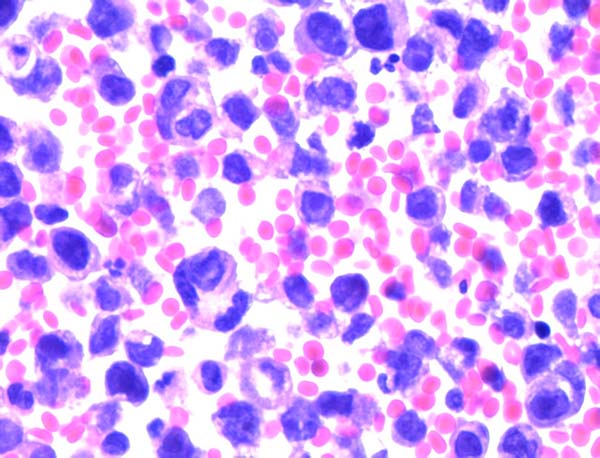

胸水传统细胞学涂片:镜下细胞量丰富,弥漫分布,细胞核大异型,部分胞浆丰富,染色质较细腻,核分裂象易见。

细胞学判读结果:符合恶性肿瘤细胞。